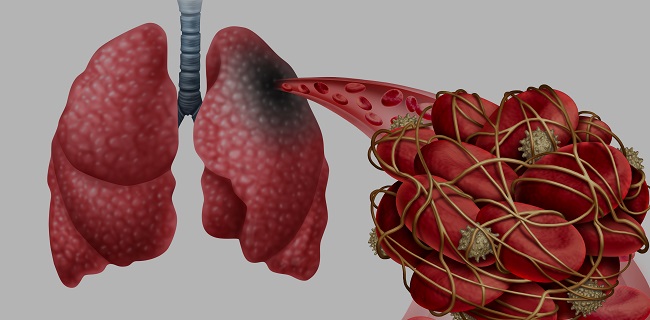

Among people hospitalized with COVID-19, preexisting heart disease nearly quadrupled their risk of acute events. |

Top Stories in Cardiology: June 2020This month, Julia Grapsa and Mary Norine Walsh describe the many ways COVID-19 affects the heart. |